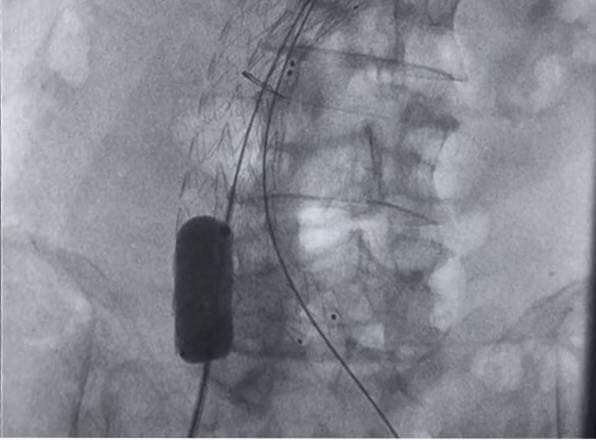

أجرى البروفيسور أحمد حاكم سليمان أستاذ واستشاري جراحات الأوعية الدموية في ألمانيا، عملية نادرة بالأشعة التدخلية لعلاج تمدد بالشريان الأورطي عن طريق تركيب دعامة تحت الأشعة ودون اللجوء للجراحة التقليدية أو فتح المريض، وقد تمت العملية بنجاح في وحدة الأشعة التداخلية بمستشفيات جامعة الزقازيق، عن طريق فريق مشترك بين قسمي الأشعة وجراحة الأوعية الدموية.

وقد ذكر الدكتور أيمن سالم رئيس قسم جراحة الأوعية الدموية، أن تلك الجراحات النادرة تتم بكفاءة عالية في مستشفيات الجامعة وتعتبر تلك الحالة الثالثة التي تتم في الجامعة في السنوات الأخيرة وفي نفس الوقت أول حالة تتم بدون اللجوء للجراحة التقليدية مما يقلل من فترة مكوث المريض بالمستشفى ويقلل من نسبة المضاعفات.

وأوضح الدكتور أحمد عوض بيصار مدرس الأشعة التداخلية بجامعة الزقازيق، أن تخصص الأشعة التداخلية يعتبر من أحدث تخصصات الطب وأكثرها تطورا واليوم في مستشفيات الجامعة نقوم بإجراء عمليات عير تقليدية لعلاج أمراض عديدة مثل أورام الكبد والآلام المختلفة ونزيف الدماغ، كما أن لدينا أول فريق علمي في مصر بالتعاون مع قسم جراحة الأوعية الدموية لعلاج تشوهات الأوردة والشرايين.